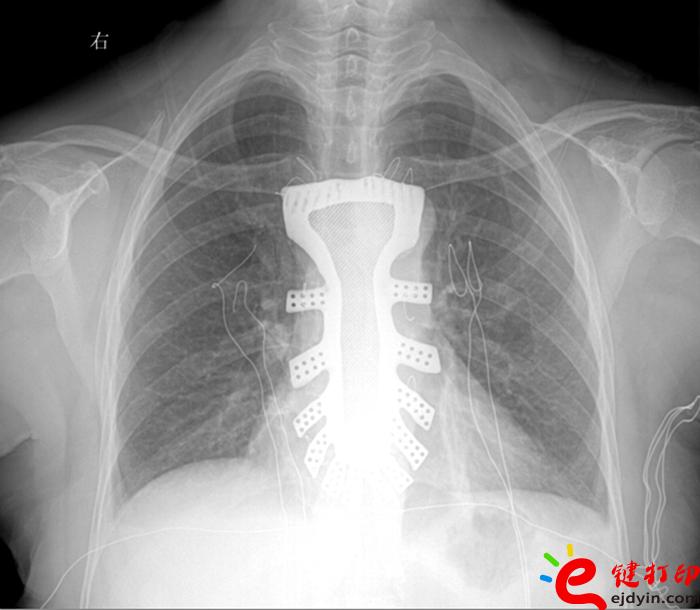

當然,“3D打印”的世界遠不止如此。據參加大會的專家和企業負責人介紹,目前“3D打印”已被運用在文化創意、文物修復、生物醫療、工業設計等多個領域。如,在航空航天器材上,一些關鍵零部件采用“3D打印”一次成型,使得其功能更加實用,重量大幅減少;在醫療領域,“3D打印”被運用于牙齒再造和骨骼修復等方面,從而使治療更加精準。